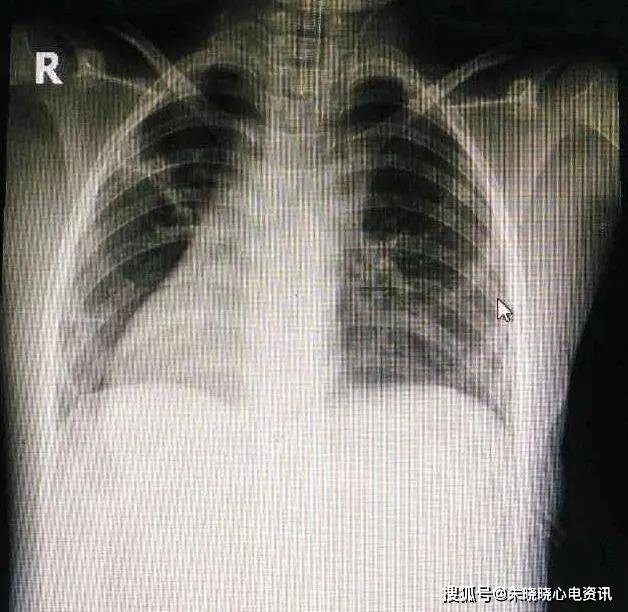

心脏片子,心脏图片

心脏旁取子弹患者成功获救

x0001:心脏平片之二

心脏x线表现